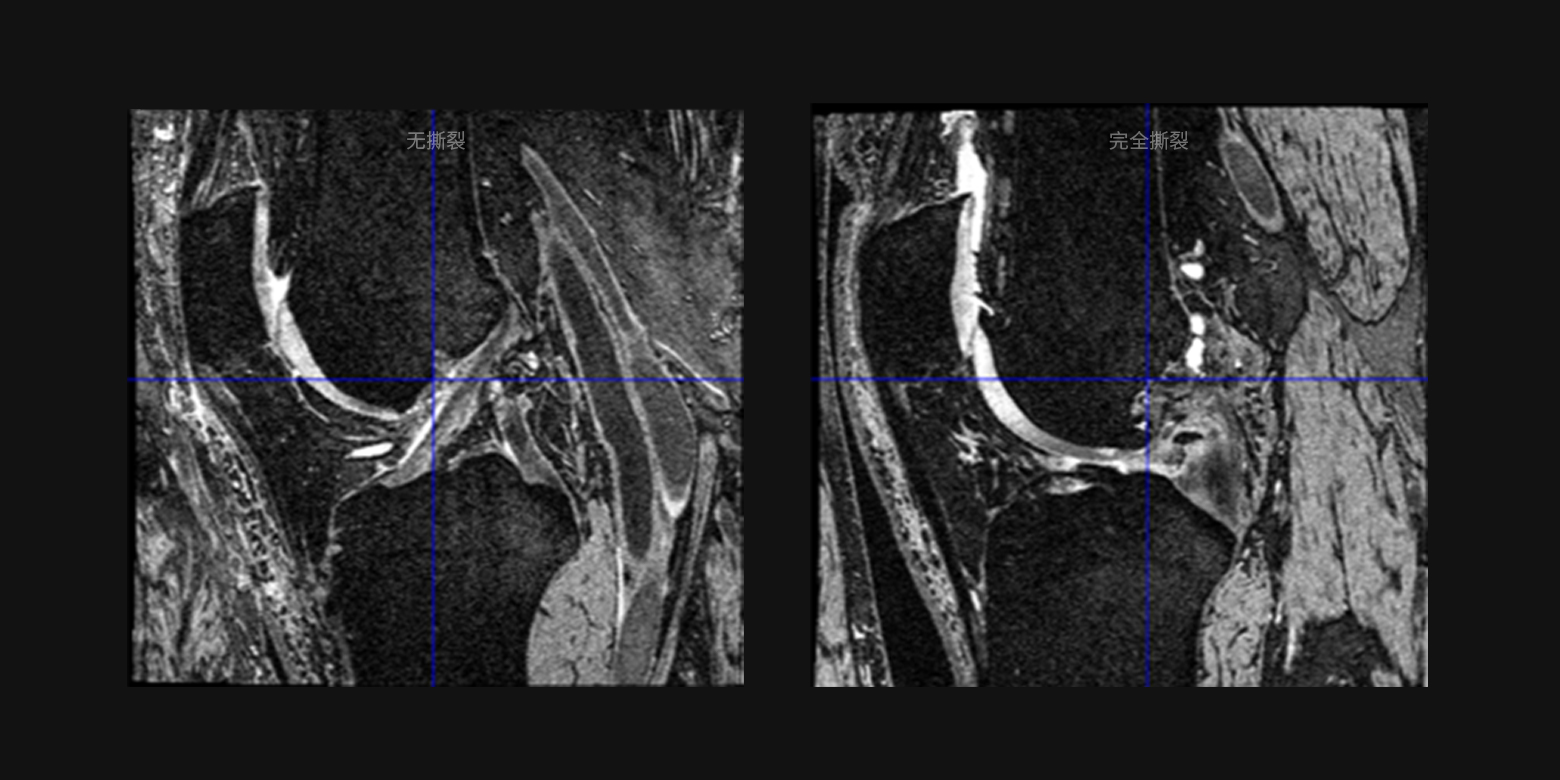

病灶良惡性鑑別和病情分級

通過對以往複雜醫學診斷的不斷學習,可滿足大範圍的疾病篩查、病情分級判斷等等的需求,例如可分辨病變是良性或惡性的鑑別,病情的分級,例如十字韌帶撕裂的分級、肺結的惡性鑑別等。